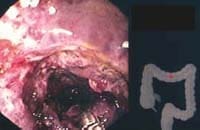

Figura 1. CI aguda leve: equimosis, petequias y erosiones superficiales cubiertas de fibrina.

Endoscópicamente, se encontraron áreas de equimosis, eritema, mucosa violácea en los 15 pacientes, y úlceras y membranas fibrinoides en el 67% de ellos (Figuras 1, 2, 3, 4 y 5).

Finalmente, encontrar lesiones ulceradas circunferenciales y membranas gris ratón es signo de mal pronóstico, como sucedió en tres pacientes. Los cuales presentaron complicaciones tales como estenosis en dos de ellos y una perforación con posterior muerte por fibrilacion ventricular.

Figura 5. CI aguda severa: mucosa pálida, membranas grisácesas (piel de ratón) que compromete toda la circunferencia.